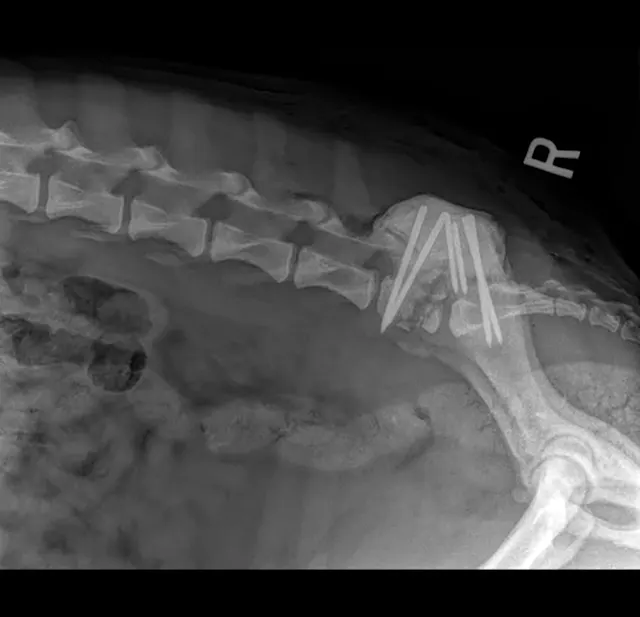

Survey radiography of the lumbar spine, pelvis, and hips is recommended. Common abnormalities identified in patients with LS disease include vertebral spondylosis, sclerosis of the vertebral end plates, and collapsed L7-S1 disk space. Stress radiography may exacerbate a lumbosacral step, which can further aid in diagnosis. Radiographs are also recommended to help rule out metastatic disease, diskospondylitis, trauma, or luxation (Figures 1-3).

Figure 1

Right lateral radiograph of a dog demonstrating L7 fracture. Images courtesy of Dr Tammy Stevenson.

Distraction and stabilization may be required to correct ventral subluxation of S1, prevent further lumbosacral instability, or decompress the L7 spinal nerve in the intervertebral foramen. In a single study, an average of 78% of dogs undergoing surgery had an excellent or good outcome, as assessed by both owners and veterinarians.12 Careful preoperative consideration is recommended for patients with urinary and/or fecal incontinence, as surgical resolution of incontinence can be poor. The same study documented that the presence of urinary and/or fecal incontinence before surgery is the only individual clinical sign that significantly affects outcome.12,13